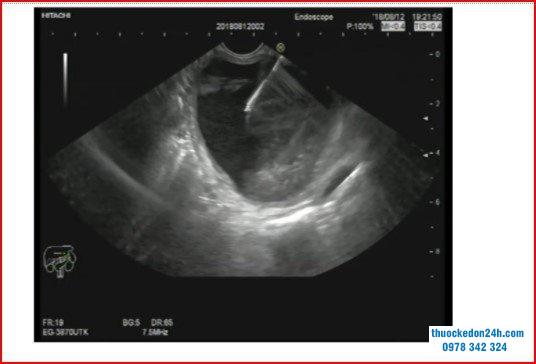

Nội soi hút kim nhỏ có hướng dẫn siêu âm của một khối u nang tuyến tụy.